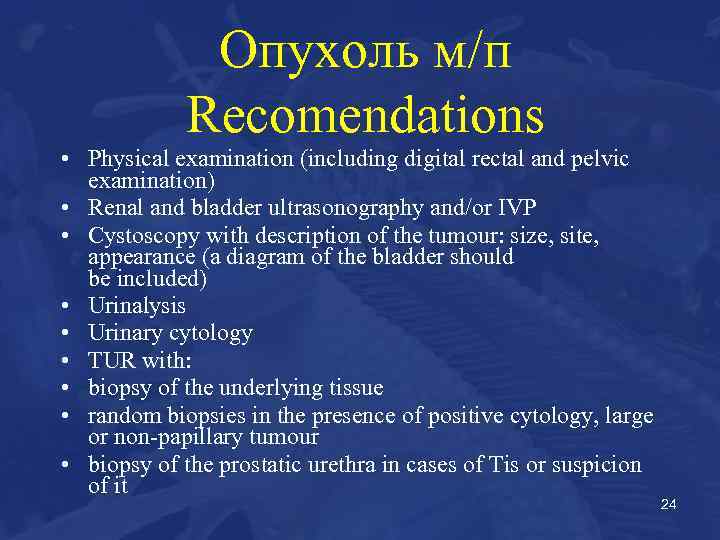

Опухоль м/п Recomendations • Physical examination (including digital rectal and pelvic examination) • Renal and bladder ultrasonography and/or IVP • Cystoscopy with description of the tumour: size, site, appearance (a diagram of the bladder should be included) • Urinalysis • Urinary cytology • TUR with: • biopsy of the underlying tissue • random biopsies in the presence of positive cytology, large or non-papillary tumour • biopsy of the prostatic urethra in cases of Tis or suspicion of it 24